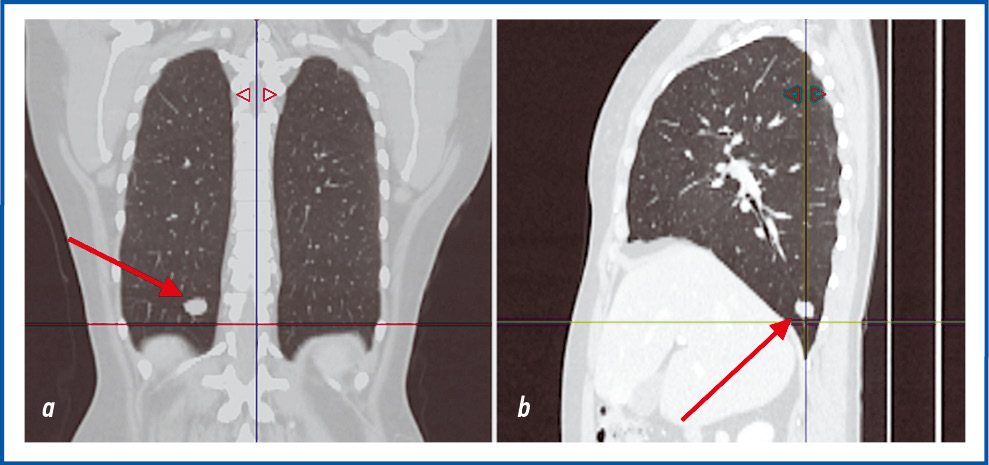

При патологоанатомическом исследовании макропрепарата: матка представлена многоузловым конгломератом общим размером 30×28×20 см, при разрезе матки выявлялось множество плотных узловых образований желтовато-серого цвета, волокнистого вида, размером от 0,5 до 2 см. Образование располагалось преимущественно по передней стенке ТМ с прорастанием всех слоев. В яичниках и тубоовариальных связках слева и справа определялись множественные опухолевые узлы (ОУ) аналогичного строения ОУ в матке, размерами от 1 до 13 см. В тазовых ЛУ справа и слева обнаружены аналогичные плотные узлы от 0,5 до 1 см в диаметре. Образование мягких тканей левого бедра представлено ОУ аналогичного строения размером 3×2,5×1,5 см. При микроскопическом исследовании все образования представлены доброкачественной опухолевой тканью в виде переплетающихся гладкомышечных волокон с низкой митотической активностью опухолевых клеток (ОК) без полиморфизма, очагов некроза и кровоизлияний (рис. 8). Морфологическая картина соответствовала ЛММ, мягких тканей левого бедра, тазовых ЛУ (рис. 9), обоих яичников и тубоовариальных связок ТМ.

Рис. 8. Микрофотография метастатической ЛММ (доброкачественная мезенхимальная опухоль, представленная пучками переплетающихся веретеновидных клеток гладкомышечного типа без атипии). Окраска гематоксилин-эозином, ×100.

Fig. 8. Microphotograph of metastatic ULM (benign mesenchymal tumor) represented by bundles of interwoven spindle-shaped smooth muscle cells without atypia. Hematoxylin and eosin staining, ×100.